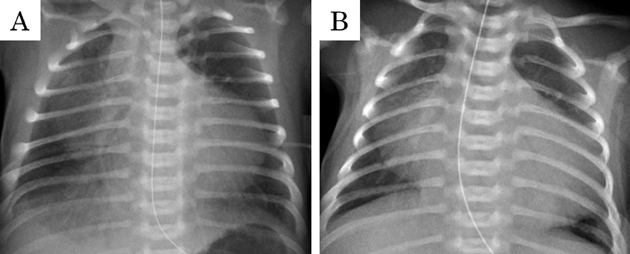

在胎35週の心室中隔欠損を伴わない肺動脈閉鎖における両側肺動脈絞扼術を用いた肺血流制御Bilateral Pulmonary Artery Banding to Regulate Excessive Pulmonary Blood Flow in Pulmonary Atresia with an Intact Ventricular Septum at 35 Weeks of Gestation